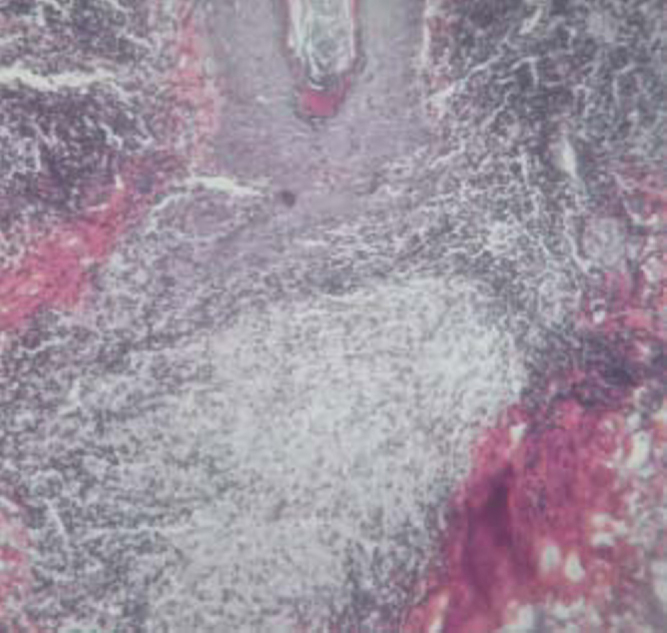

In both the cases, haematological and biochemical investigations including serum calcium were normal, mantoux test was negative, radiograph of chest and pulmonary function tests were normal. Histopathology of the lesion revealed discrete, well defined non caseating epithelioid cell granulomas with mild lymphoid infiltrate scattered throughout the dermis (Fig 3). Reticulin stain revealed reticulin fibres in and around the granulomas. No acid fast bacilli or fungal elements were seen. Serum angiotensin converting enzyme (SACE) levels were 60 IU/ml in the first case and 82 IU/ml in the second case (normal range 18-67 IU/ml).

Fig 3.

Sarcoidal granuloma (H & E stain × 100)

Sarcoidosis needs to be distinguished histopathologically from lupus vulgaris and leprosy as they all have epithelioid cell granulomas. While the granulomas in lupus vulgaris are caseous and present in the upper dermis, those in leprosy are mainly around dermal nerve twigs and admixed with abundant lymphocytic infiltration. In contrast, sarcoidal granulomas are discrete, distributed uniformly in the dermis and surrounded by sparse lymphocyte cuffing (‘naked tubercles’), with fine reticulin fibers in and around the tubercles [4].